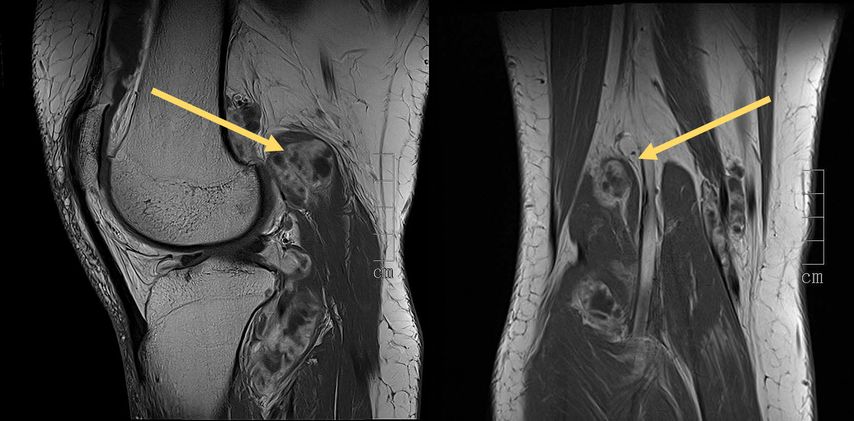

Der tenosynoviale Riesenzelltumor (TSRZT), welcher im deutschsprachigen Raum früher als PVNS (pigmentierte villonoduläre Synovitis) bezeichnet wurde, stellt wohl mit ca. 1,8 Neuerkrankungen pro 100000 Einwohnern pro Jahr die größte Gruppe an Läsionen dieser Art am Bewegungsapparat dar. Der Nomenklatur der WHO folgend soll der Terminus PVNS nicht mehr verwendet werden, da es sich histologisch um dieselbe Entität wie TSRZT handelt.6–9 Der TSRZT der Weichteile darf nicht mit dem des Knochens verwechselt werden. Der TSRZT kann ursächlich für synoviale Verdickungen und ein Überwachsen sein, wie in Abbildung 1 dargestellt. Normalerweise produziert die Synovia eine kleine Menge einer viskösen Flüssigkeit, welche die Gelenke bzw. den Knorpel „schmiert“ und so zu einem physiologischen Bewegungsablauf beiträgt. Der TSRZT produziert vermehrt diese Flüssigkeit, was Schwellung und Schmerz nach sich zieht. Oftmals wird dieser Zustand mit Erkrankungen aus dem rheumatoiden Formenkreis verwechselt. Im Falle des Vorliegens eines TSRZT ist die Dunkelziffer groß.8 Diese gutartigen Tumoren entstehen aus synovialem Gewebe: Gelenken, Sehnenscheiden oder Bursen. Große Unterschiede gibt es im lokalen Verhalten, man unterscheidet eine lokal aggressive (diffuse) von einer nodulären Wachstumsform (Abb. 2). Eine Metastasierung oder eine sarkomatöse Transformation sind extrem selten. Die diffuse Form wird von vielen als schwieriger in der Behandlung wahrgenommen, da sie destruktiver wächst und eine höhere Rezidivrate hat.10–12

Abb. 2: MRT-Bilder eines intra- und extraartikulären TSRZT am Kniegelenk